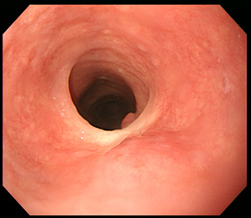

Figure 3 Endoscopic treatment of esophageal stricture.

(A) A follow-up esophagogastroduodenoscopy (EGD) at 1 month after the procedure revealed significant stricture at esophagus. (B) Repeatitive endoscopic balloon dilation was performed. (C) After 8 times of endoscopic ballooning, esophageal stricture was resolved.